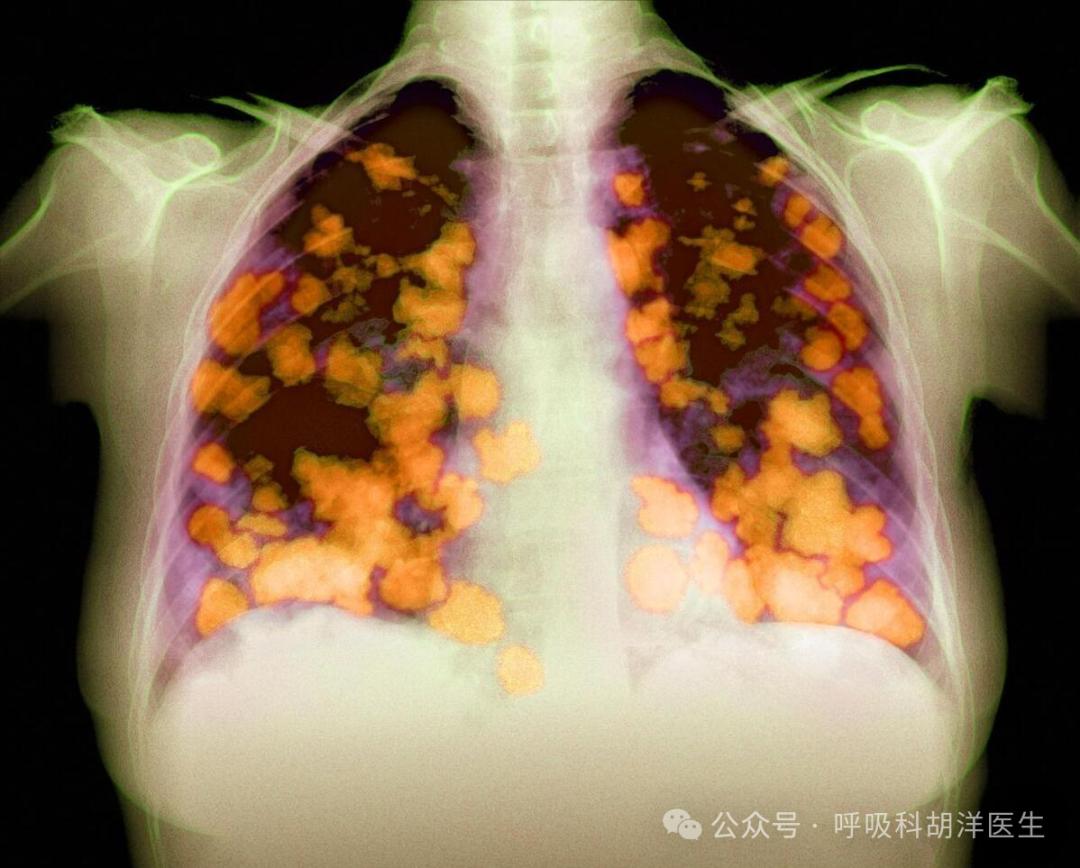

肺癌有四种类型,包括鳞癌、腺癌、大细胞肺癌和小细胞肺癌。每种类型都分为低分化程度和高分化程度。前者比后者活得短。小细胞肺癌之所以可怕,是因为小细胞肺癌很少分化。

有没有类似甚至更可怕的类型的小细胞肺癌?当然也有。比如腺癌恶性程度比较高,腺癌也分为病理亚型,如贴壁型、腺泡型、乳头型、微乳头型,其中微乳头型比例较高的腺癌恶性程度较高。还有一种基因类型叫做缺乏SMARCA基因的肺癌,发展迅速,甚至不逊色于小细胞肺癌。

此外,还有一些特殊类型的肺癌,如肉瘤样癌,也是肺癌中位存活不超过一年的类型。它的特点是看起来像肉瘤,但实际上是癌症。两者的区别在于癌细胞来源不同。前者一般恶性程度较高,肉瘤样癌基本没有很好的治疗方法。生存时间也比较短。